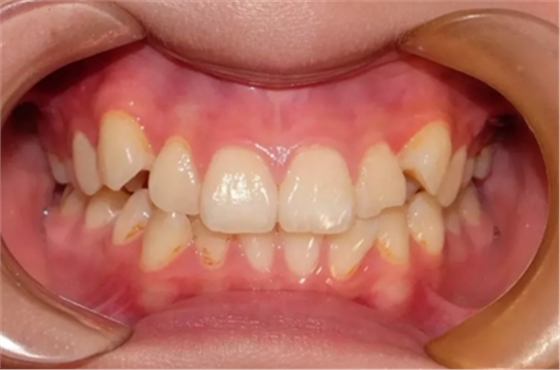

01 反頜

反頜通常被稱為“地包天”,也有些是個別牙反頜。該如何避免?